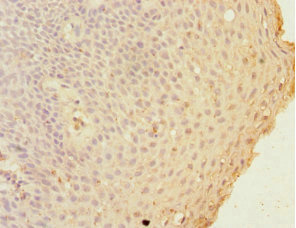

Immunohistochemistry of paraffin-embedded human tonsil tissue using CSB-PA009307DSR1HU at dilution of 1:100